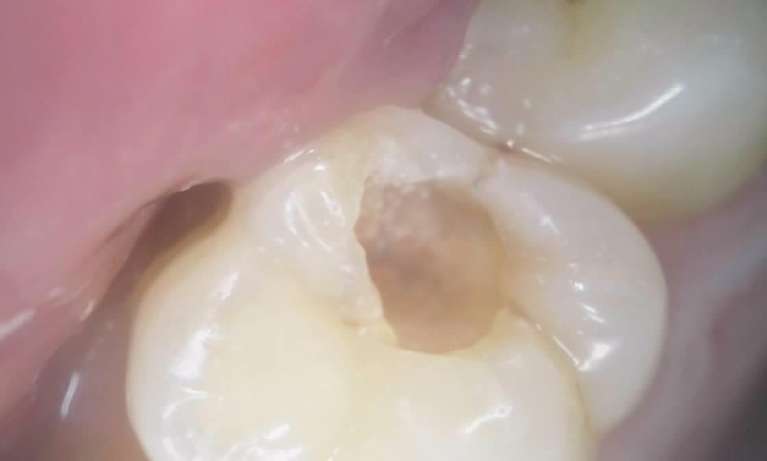

We take great pride in the services we perform in our office. We always try to not only meet your expectations, but we also try to exceed them. There are many types of services that we perform in our office, as well as others that we perform in coordination with highly skilled specialists. We have compiled a few examples of the treatments that we have performed. We are proud to say that these are the usual results our patients expect to see.

The photos are not retouched, nor are they taken by a professional photographer. These are just the routine treatment photos that we take and the results that we see every day. They are by no means a comprehensive catalog of the procedures that we perform. They are just a small sample of some of the results you can expect when you seek treatment in our office.